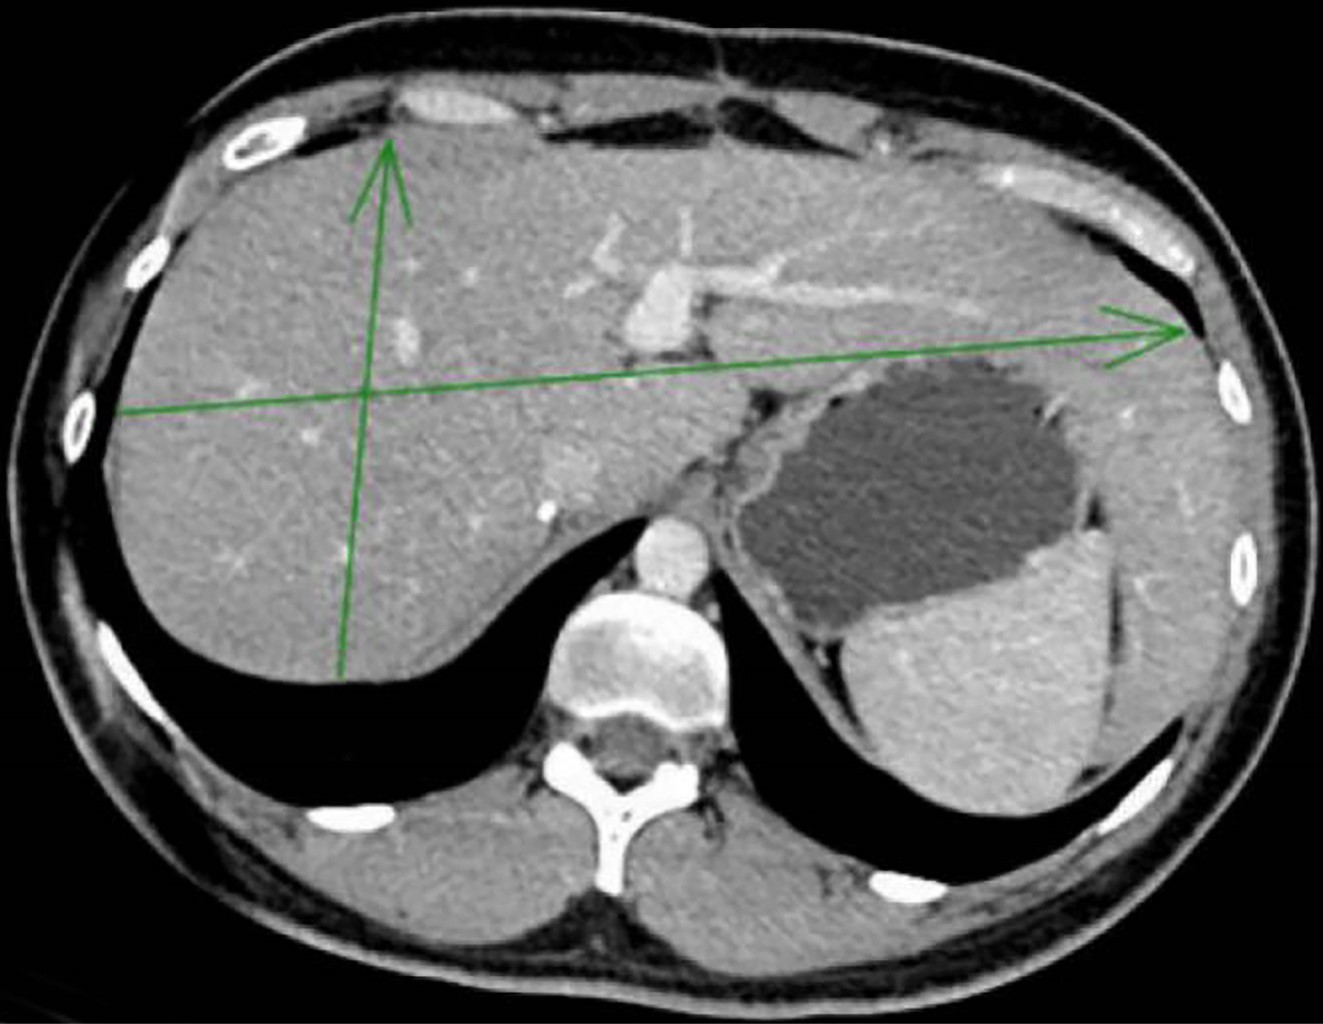

A la exploración física, el paciente se encontró en buenas condiciones generales, se propuso segmentectomía V-IVB; sin embargo, por antecedente de infarto agudo de miocardio se sometió a quimioembolización transarterial (TACE), después se solicitó una tomografía axial computarizada (TAC) con presencia de lesión hipodensa mal definida en segmento V (Figuras 1 y 2), por lo que es sometido a colecistectomía y resección de segmento V y VI, con reporte de carcinoma hepatocelular moderadamente diferenciado con patrón trabecular y sólido focal, sin células neoplásicas en el lecho quirúrgico. Al presentar metástasis peritoneales dentro de su seguimiento, se decidió su adyuvancia con quimioterapia, el paciente mostró adecuada respuesta al disminuir las metástasis peritoneales 10 años después. En la actualidad, el paciente sigue vivo en adecuadas condiciones clínicas.

Figura 1